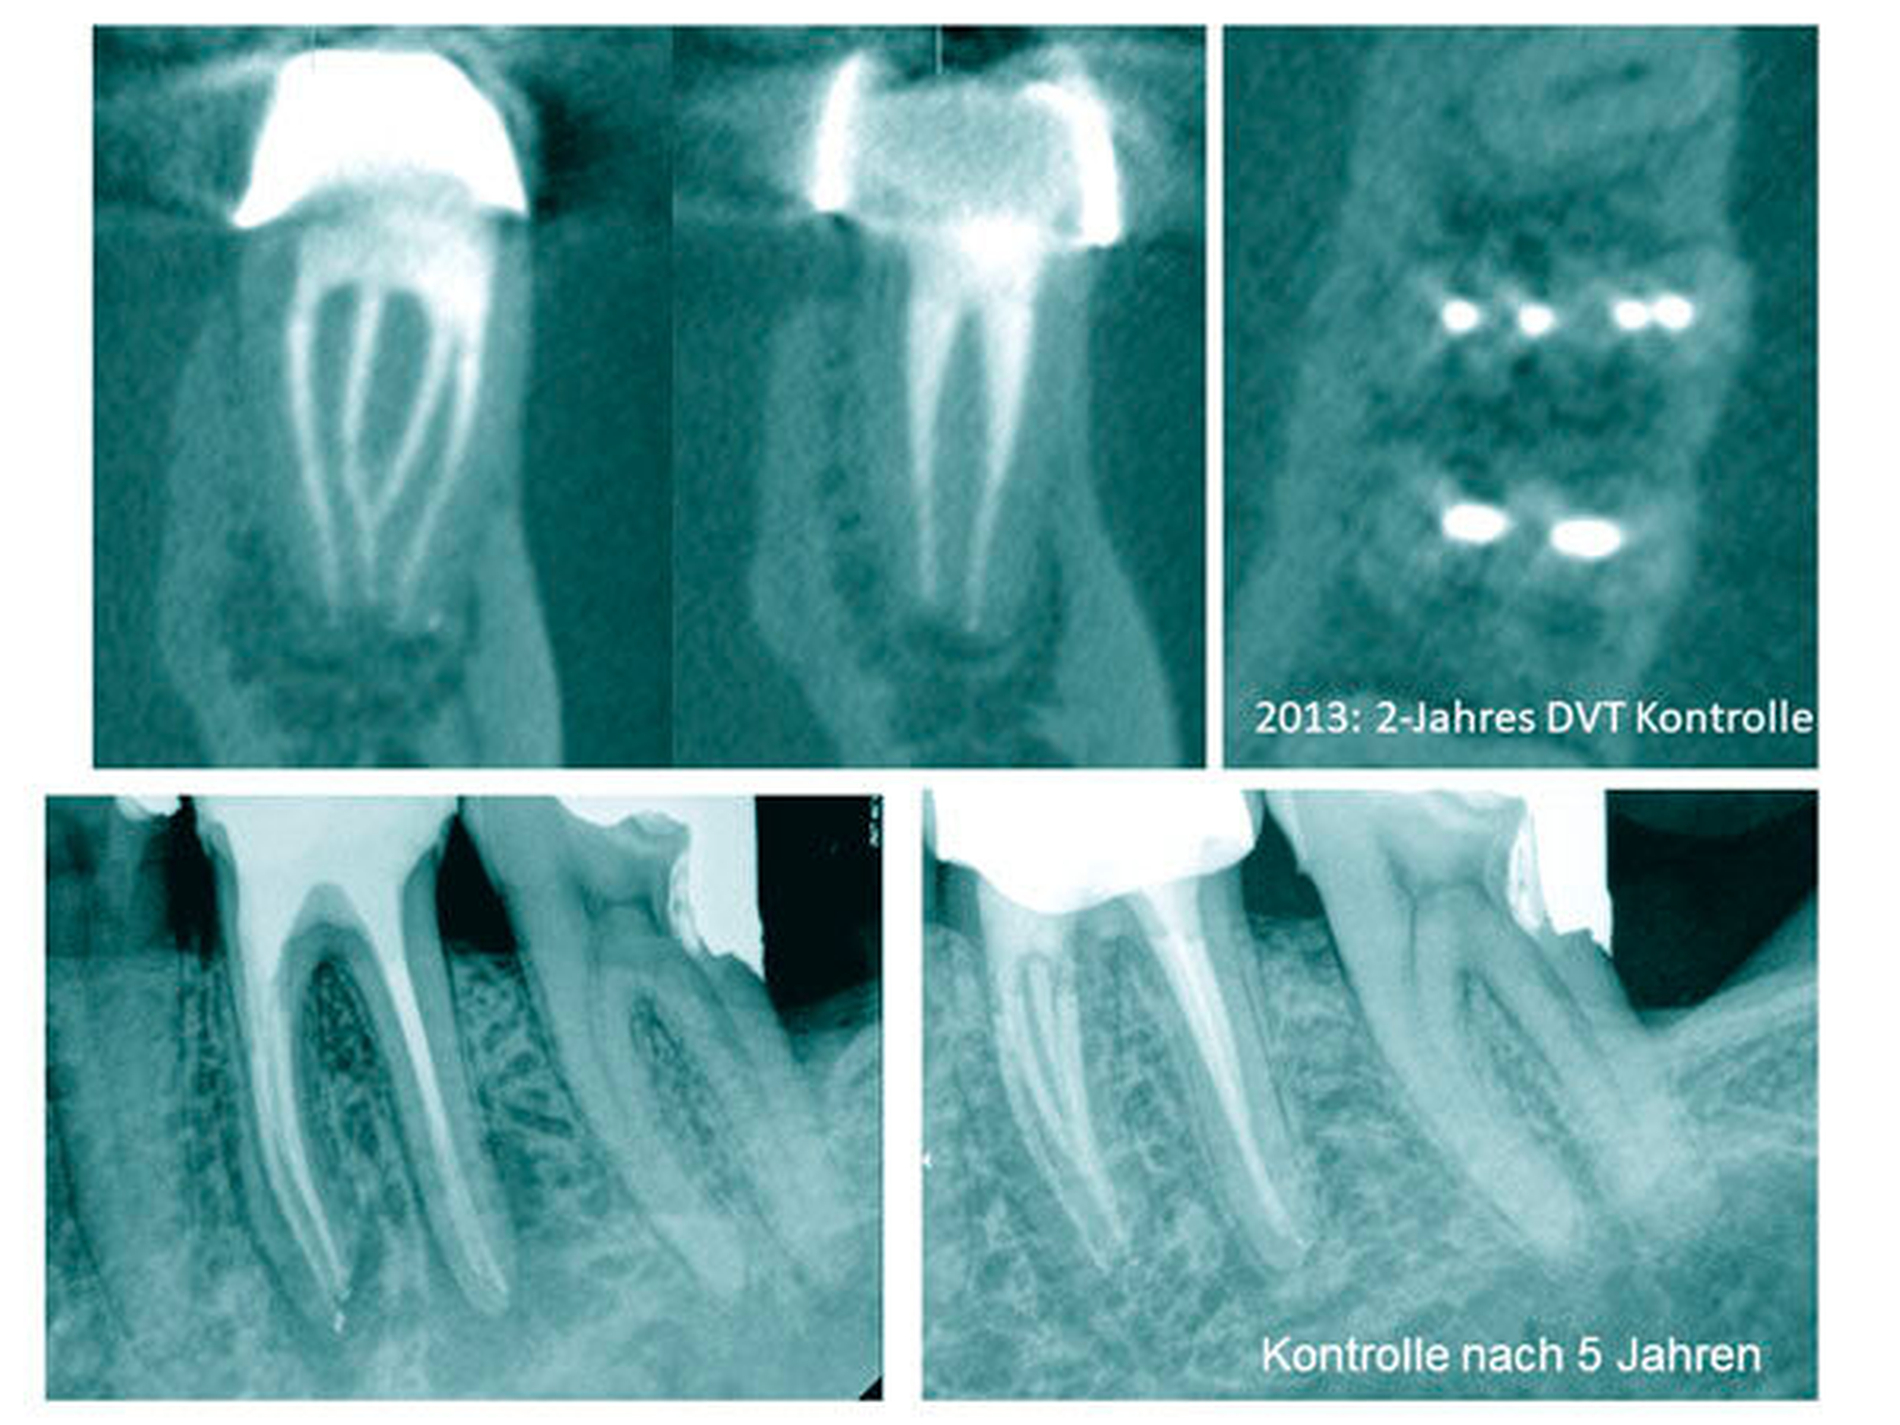

Die Komplexität der Anatomie wird neben den Kanalkrümmungen durch die Isthmen, die lateralen Kanäle und die apikalen Verästelungen bestimmt. Problemstellen sind nicht einsehbare Bereiche von Wurzelkanal-Krümmungen, verschiedenen Wurzelkanalquerschnitten und akzessorischen Kanälen sowie laterale Kanäle, Furkationskanäle, Ausbuchtungen und multiple apikale Foramina, sogenannte apikale Deltas. Zudem ist die distale Dentinwand der mesialen Wurzel sehr dünn und als sogenannte „danger zone“ bekannt [Abou-Rass et al., 1980] [Harris et al., 2013] (Abbildung 3). In der Studie von Harris et al. [Harris et al., 2013] konnte gezeigt werden, dass die distale Wanddicke in der mesialen Wurzel (1,5 mm unterhalb der Furkation) mit Werten von 0,81–1,22 mm am dünnsten war. In einer anderen Studie wurden vergleichbare Ergebnisse mit einer durchschnittlichen Dentindicke von 1,2–1,3 mm gemessen [Berutti & Fedon, 1992] (Messung ebenfalls 1,5 mm unterhalb der Furkation).

Daher gilt es bei allen Maßnahmen zur Kanaleingangserweiterung die meist sehr konischen Instrumente mit Bedacht zu verwenden und mehr gegen die mesiale Kanalwand abzutragen.